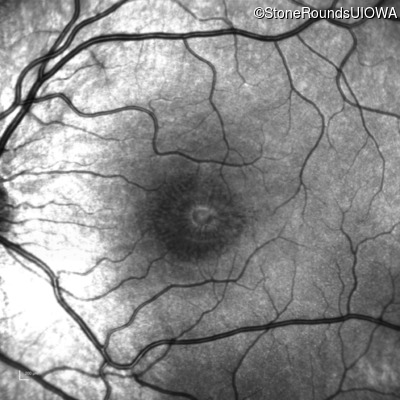

Infrared Fundus Photograph - Left - 20/40

Exemplar